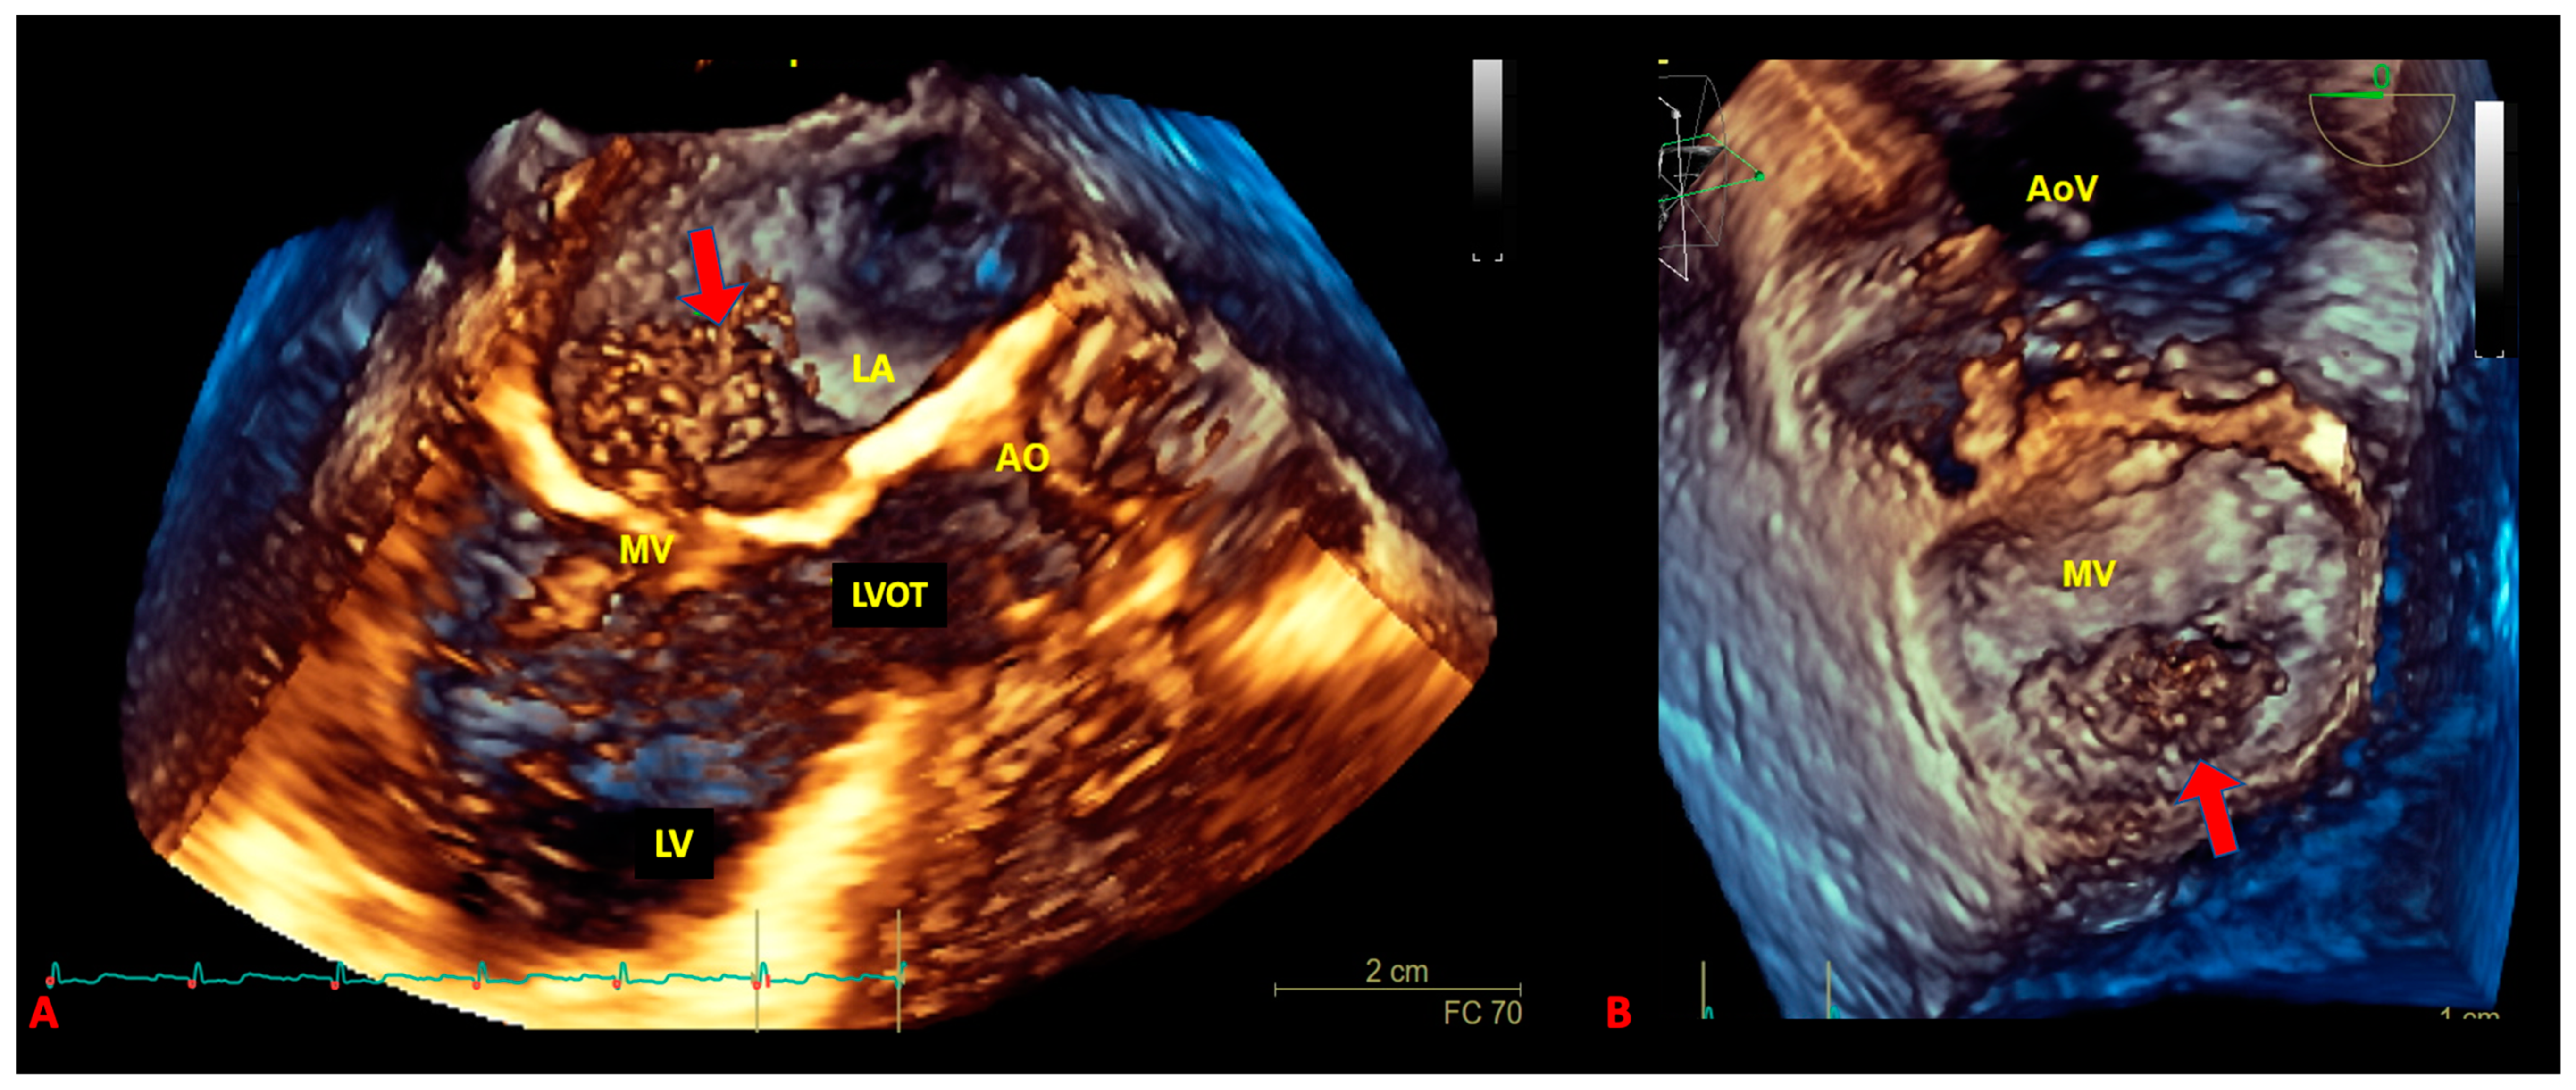

3. The Role of Echocardiography in pSTS-h